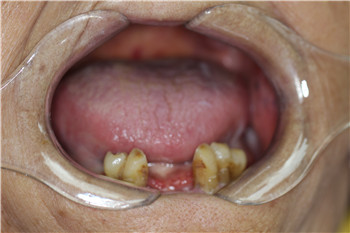

种牙前

在医院,麦芽种植牙专家游勤波医生为田奶奶检查一番后,发现田奶奶由于长期缺牙,口腔内环境堪忧,需要先进行牙周治疗后再施以种植牙手术。而且由于田奶奶年龄比较年迈,需要进一步调理,便制定了即刻用种植牙修复方案。